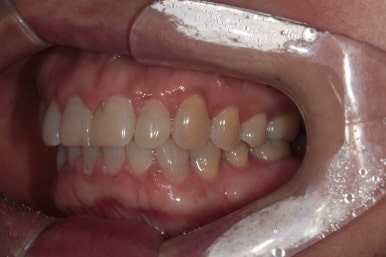

정면에서 본 사진입니다.

잘 모르실 수도 있겠지만, 잇몸이 염증이 생겨 치주염으로 인해 빨갛게 변하신 것을 보실 수 있어요.

즉, 잇몸질환-만성치주염을 갖고 계신 상태였죠.

위 앞니 (중절치)는 치아 사이 틈을 메우기 위해 예전에 레진치료를 받으신 상태였는데, 치료받으신지 오래되어 레진 충전물의 색이 변하고 어색한 모양을 띄고 있습니다.

앞면, 양쪽 옆면 모두 아주 깔끔하게 유지되고 있네요!

기억하고 있으실지 모르겠지만, 전반적으로 나타내고 있던 잇몸의 붉은색도 대부분 사라져 있는 상태입니다.